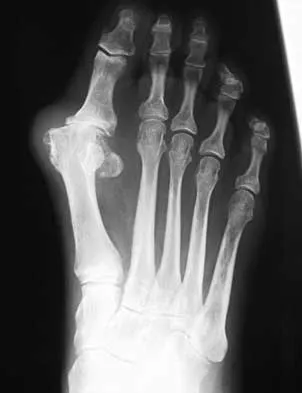

Question 58

A 61-year-old woman has increasing pain in her left great toe. She states that she has had discomfort for years but now has pain with all shoe wear. A radiograph is shown in Figure 35. To provide the most predictable pain-free result, treatment should consist of

Explanation